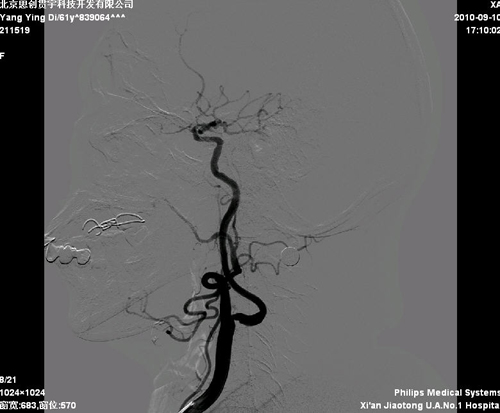

脑血管造影:右颈内动脉起始部30%狭窄;左颈内动脉起始部70%狭窄,基底动脉50%狭窄。

该患者诊断明确,有症状性颈动脉狭窄,且狭窄>50%,有进一步处理指征。患者左侧颈内动脉存在‘kinks征’,开口处迂曲,脑保护装置及支架输送系统可能难以通过病变,且患者颈动脉分叉不高,选择CEA更为合适。但此患者颈内动脉远端虹吸段也存在狭窄,患者此次的症状可能与二者同时相关,也可能只与其中一处相关,因此,处理颈内动脉起始部病变对预防远期同侧脑卒中有限。